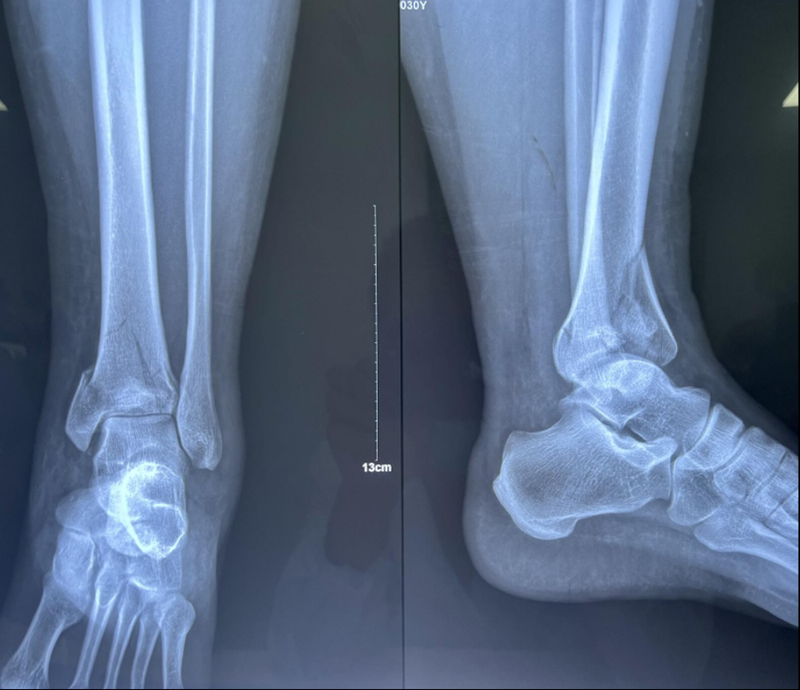

x男,30岁,体重100kg,在五楼擦玻璃时坠落到四楼致伤2天。

诊断:左胫骨平台后柱骨折,后交叉韧带撕脱骨折,左踝关节pilon骨折3型。

术前影像学资料:

图8 Pilon骨折3型